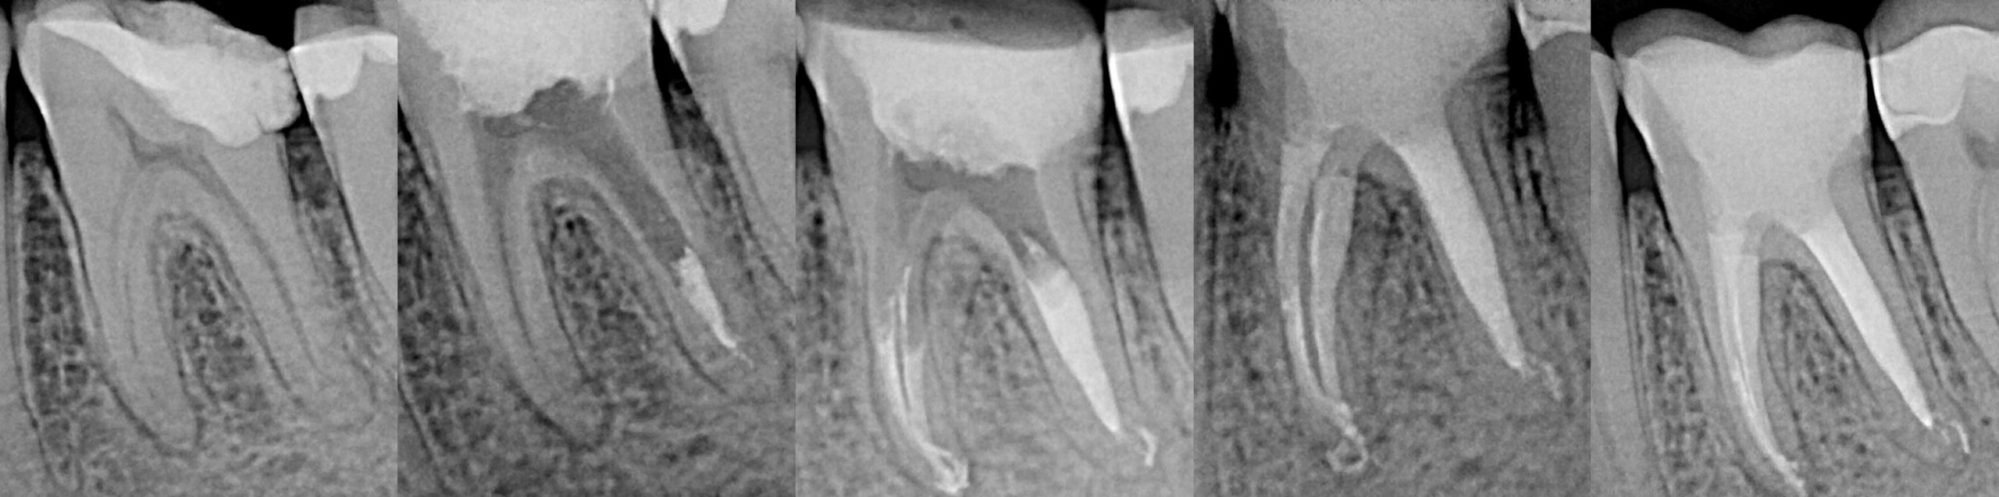

TECHNIKA LECZENIA KANAŁOWEGO ZĘBA

Na podstawie zdjęcia rentgenowskiego określa się kształt i długość kanału bądź za pomocą specjalnego urządzenia mierzy się jego długość. Potem lekarz otwiera wejścia do kanału, chroniąc ząb koferdamem, czyli specjalną gumą, zapewniającą sterylność oraz chroniącą przed środkami chemicznymi służącymi do oczyszczania kanału. Używa się do tego zarówno specjalistycznego sprzętu, jak i nowoczesnych mikroskopów, pozwalających na uzyskanie dokładnego obrazu leczonego zęba. Ostatnią czynnością jest wypełnienie materiałem światłoutwardzalnym i zabezpieczenie zęba przed dostaniem się i rozwojem bakterii mogących wywołać wtórny stan zapalny.

Zarówno ziarniniak okołowierzchołkowy, jak i torbiel zębopochodna uszkadzają struktury okolicznej tkanki kostnej. Podobny proces jeszcze do niedawna był książkowym wskazaniem do interwencji chirurgicznej (resekcja wierzchołka korzenia, hemisekcja korzenia zęba wielokorzeniowego) lub nawet usunięcia zęba.

Przy obecnym stanie wiedzy praktycznej wynikającej z doświadczeń pokoleń lekarzy oraz szerokim dostępie do nowoczesnej, specjalistycznej aparatury medycznej, metody terapii stały się mniej inwazyjne, bardziej przewidywalne, mniej radykalne i z założenia prowadzą do zachowania zęba w jamie ustnej.

By uniknąć niedokładności leczenia, oprócz sumiennego wykonania procedur należy diagnostycznie kontrolować każdy etap leczniczy przy użyciu rtg. Szansą dla niedokładnie wypełnionego kanałowo zęba jest jego powtórne leczenie endodontyczne, zwane REENDO.

LECZENIE ENDODONTYCZNE ZE SKOMPLIKOWANĄ ANATOMIĄ ZĘBA